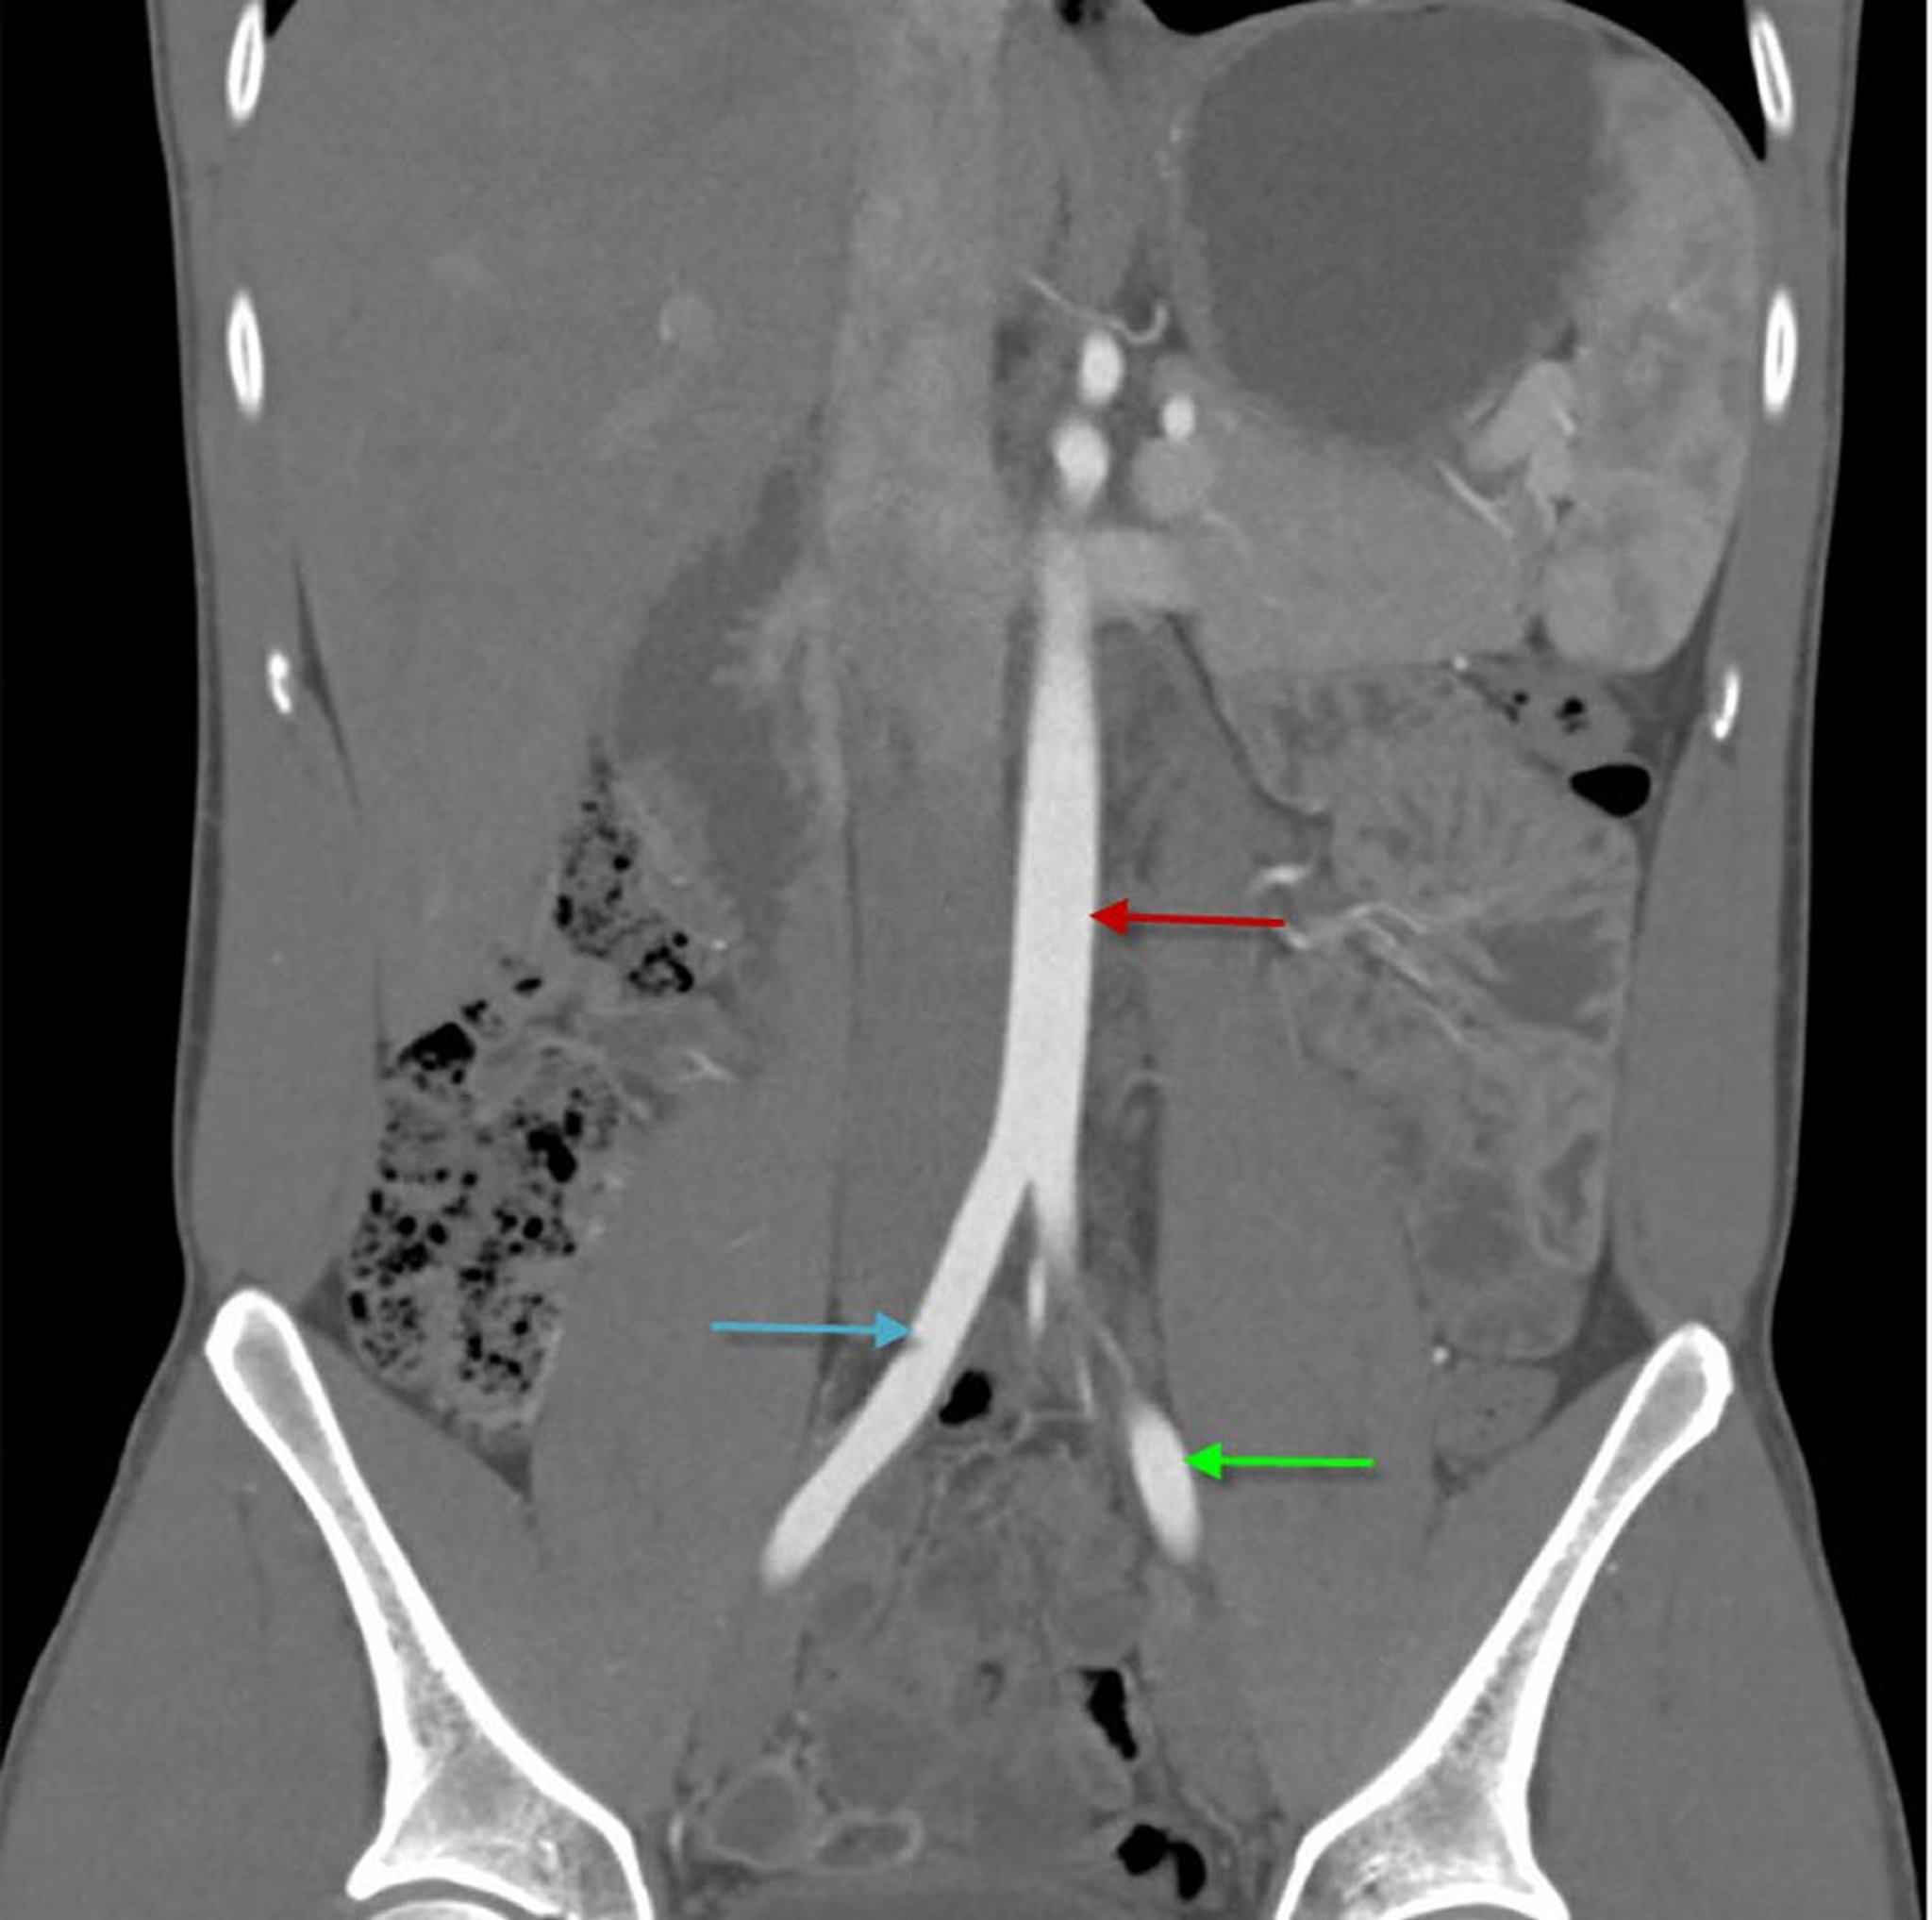

CTA (koronale Ansicht) des Abdomens mit Darstellung der abdominalen Aorta

Dieses Bild zeigt die abdominale Aorta (roter Pfeil), die sich in die rechte (blauer Pfeil) und linke (grüner Pfeil) A. iliaca communis teilt.